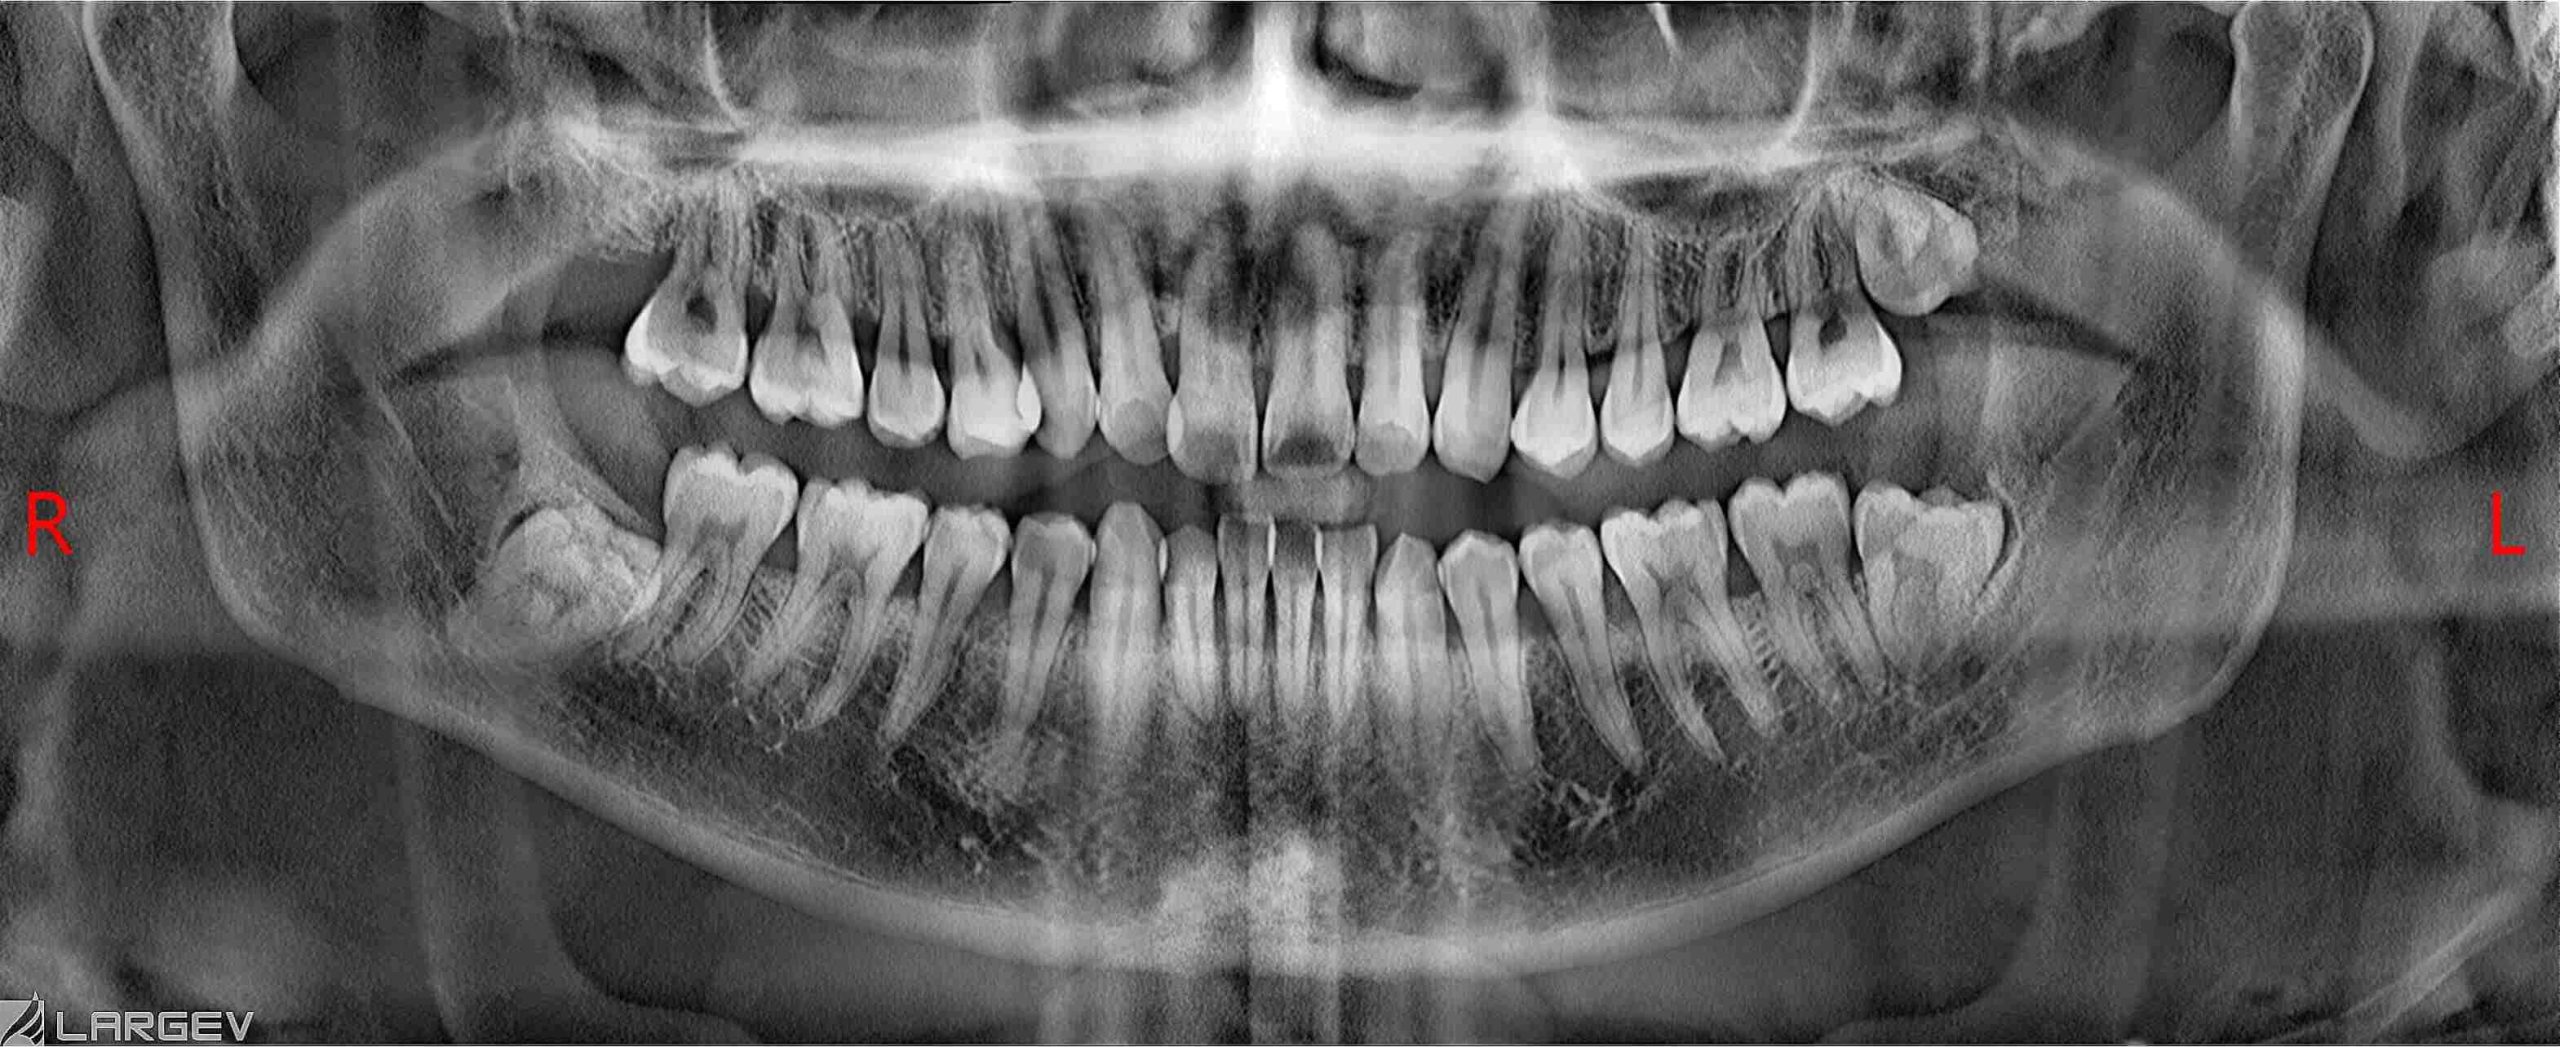

2-Dimensional (2D) Digital X-rays

2D digital X-rays capture detailed images of your teeth and surrounding structures. These X-rays are essential for routine examinations, allowing us to detect cavities, monitor tooth development, and assess bone health with precision.